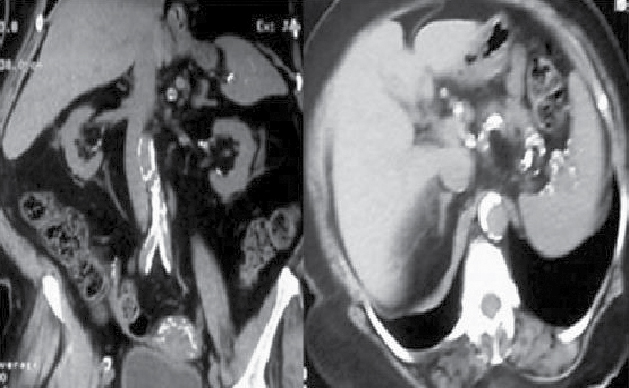

At our center, we screened pre-ESRD (end-stage renal disease) [CKD stage 4 and 5] patients for the presence of vascular calcification using digital X-ray lumbar spine and multislice CT scan (Fig. 4). The prevalence of vascular calcification (abdominal aortic calcification) in pre-ESRD patients was 75% (73.6% and 81.8% for CKD stages 4 and 5, respectively). The median aortic calcification index was 19.9% in all patients, 18.5% in CKD stage 4 and 21.4% in CKD stage 5. Decreased glomerular filtration rate may be associated with the presence and extension of abdominal aortic calcification in pre-dialysis CKD stages 4 and5.35

Figure 4. Multislice computed tomography image of abdominal aorta showing multiple calcification sites.